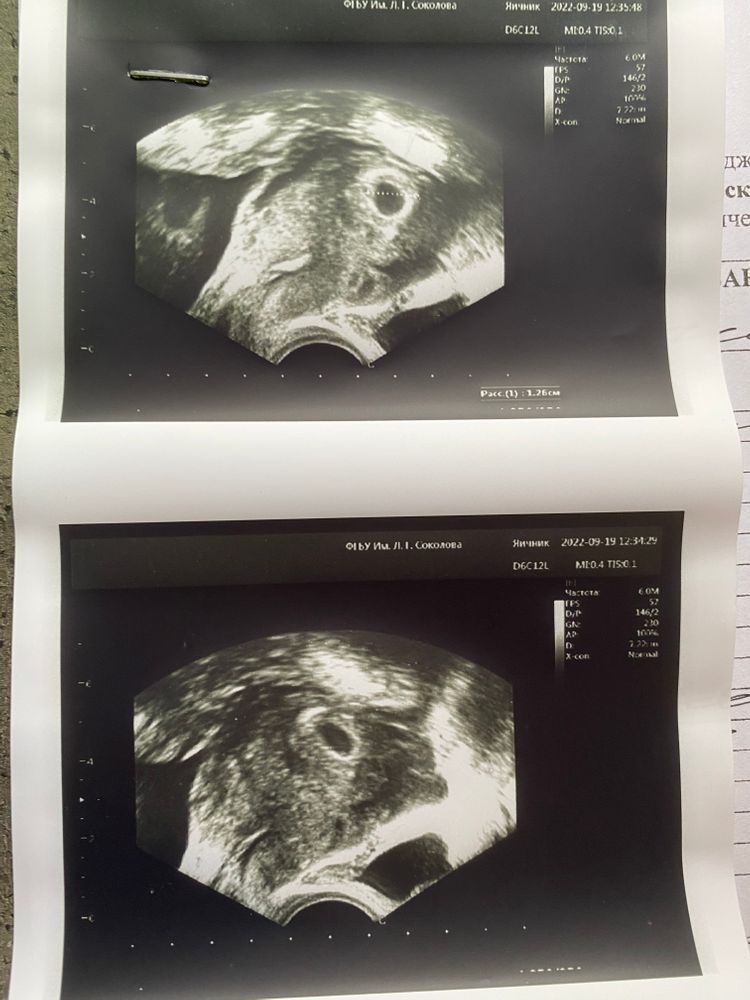

Плодное яйцо УЗИ 20 дпп

Помогите, пожалуйста, разобраться в УЗИ. Врач сказала, что плодное яйцо находится на дне матки. Также сказала, что это не очень хорошо, так как эндометрий именно на в этом месте тонкий и возможно прерывание беременности. Однако не было рекомендовано увеличить дозировку эстрогенов. Через 10 дней будет контроль узи и консилиум врачей по данной ситуации. Я всегда думала, что эндометрий в матке при наращивании распределяется равномерно.